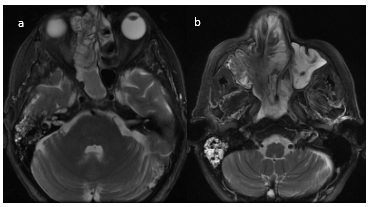

En secuencia T2 sin contraste, la lesión presenta áreas hiperintensas y de baja señal, determinando marcado desplazamiento del tabique nasal y oblitera trompa de Eustaquio derecha, con ocupación de celdillas mastoideas y oído medio homolaterales (Figura 8–9-10).